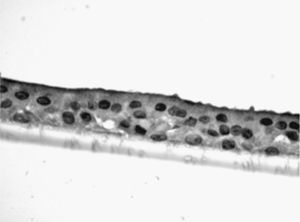

Estudio de la respuesta al humo de tabaco en cultivos de células epiteliales diferenciadasLas muestras de biopsia bronquial fueron depositadas en medio de cultivo celular, donde se mantuvieron, tras varios pases, hasta que formaron placas confluentes de células epiteliales primarias. Una vez obtenidas estas placas celulares, fueron depositadas en inserts de cultivo (8,25×104 células/insert) (Transwell, Corning Costar, Buckinghamshire, Reino Unido) con medio de diferenciación (50% DMEM), medio de crecimiento basal epitelial (Clonetics, Reino Unido) durante 7 días hasta su confluencia. Tras esta, las células fueron tripsinizadas y nuevamente cultivadas hasta su confluencia. Esta maniobra fue repetida en 2 o 3 ocasiones. Tras este periodo, las células fueron cultivadas durante otros 21 días en interfase aire-líquido (técnica ALI), con la superficie apical en contacto con aire y la superficie basal sumergida en medio de crecimiento, hasta lograr su diferenciación en epitelio seudoestratificado con presencia de células ciliadas y caliciformes. Esta característica se demostraba mediante el análisis de las muestras en microscopio invertido. En muestras aleatorias se procedió, tras su inmersión en parafina, a tinción mediante inmunohistoquímica con citoqueratina para demostrar su naturaleza epitelial, y con PAS-Schiff, para el estudio de la secreción de moco.

Las muestras obtenidas se cultivaron hasta lograr su diferenciación en epitelio seudoestratificado con presencia de células ciliadas y caliciformes. Debido a la dificultad que entraña la diferenciación en una interfase aire-líquido —se necesitó una media de 40 días para cada cultivo— y la escasez de material que aportaba la biopsia de mucosa, solo fue posible obtener cultivos viables en 4 pacientes, todos ellos del grupo de fumadores sanos. De cada uno de ellos se consiguieron 30 cultivos que fueron utilizados para su análisis experimental. La estimulación de las células epiteliales por exposición a humo de tabaco produjo un aumento dependiente de la dosis en la expresión génica obtenida mediante RT-PCR de Muc5AC (10,3 [1,2]) (fig. 1), IL8 (5,1 [0,3]) (fig. 2) y TNFα (4,3 [0,4] (fig. 3) tanto en el cultivo de 6 h como a las 24 h (2,5 [0,3], 2,4 [0,2] y 2,9 [0,2]) con respecto a sus valores basales. Este efecto en términos proporcionales fue más intenso en los cultivos de 6 h decayendo su expresión progresivamente. En estas condiciones experimentales sí que se observó una correlación significativa entre la concentración del extracto de tabaco y la expresión de IL8 (r=0,42; p<0,05) TNFα (r=0,39; p<0,05) y Muc5AC (r=0,47; p<0,05). Algunos de estos inserts se utilizaron para corroborar la diferenciación epitelial con presencia de células secretoras y epitelio ciliar (figs. 4 y 5).